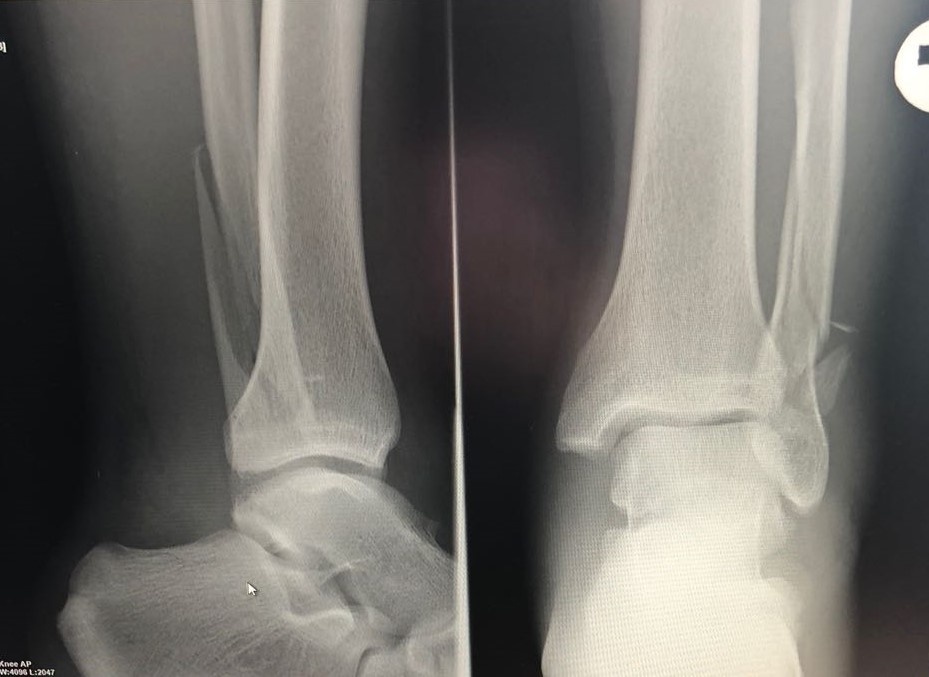

Переломы наружной лодыжки

Перелом наружной лодыжки — одно из частых осложнений при подворачивании стопы внутрь. Это происходит, когда нагрузка на кость превышает её прочность. Перелом может быть как без смещения (когда кость остаётся на месте), так и со смещением (когда кость сдвигается). Симптомы включают:

- Сильную боль снаружи голеностопа;

- Значительный отёк и синяк;

- Невозможность наступить на ногу;

- Деформацию в случае перелома со смещением.

Лечение зависит от типа перелома. Если кость не сместилась, используется гипс или специальный фиксатор на срок до 6 недель. Если есть смещение, может понадобиться операция с фиксацией кости с помощью металлических пластин и винтов. Реабилитация после перелома занимает достаточно длительное время и включает упражнения для восстановления подвижности и силы.